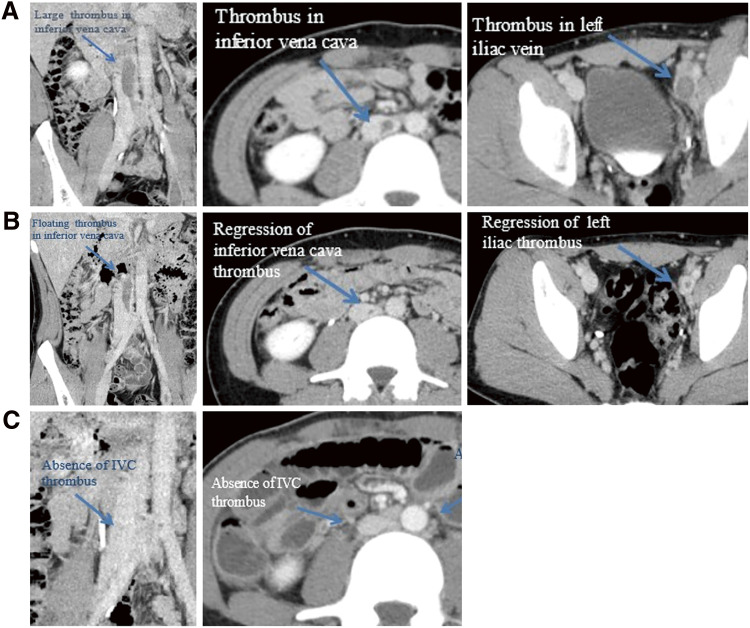

抗磷脂综合征(APS)和系统性红斑狼疮(SLE)相似,其特征是血栓栓塞事件和多种临床表现。我们经历了一个21岁的男性急性髂腔深静脉血栓形成(DVT)。原发性APS初步诊断符合标准,经多学科治疗,髂腔DVT逐渐消退。6个月后,患者主诉急性肠炎,接着是周围神经病变和蝴蝶狼疮。诊断为SLE,提示SLE发病前有APS。这个病例提出了一个问题,目前的共识,这两种疾病是明显不同的临床实体,尽管它们是密切相关的。

Antiphospholipid syndrome (APS) and systemic lupus erythematosus (SLE) are similar to be characterized by thromboembolic events and various clinical manifestations. We experienced a 21-year-old man with acute iliocaval deep vein thrombosis (DVT). Primary APS was initially diagnosed on the criteria, and after multidisciplinary treatment, iliocaval DVT was gradually regressed. Six months later, the patient complained of acute enteritis, followed by peripheral neuropathy and butterfly lupus. SLE was diagnosed, which suggested that the onset of SLE was preceded by APS. This case raises the question of a present consensus that these two diseases are clearly different clinical entities, although these are closely related.